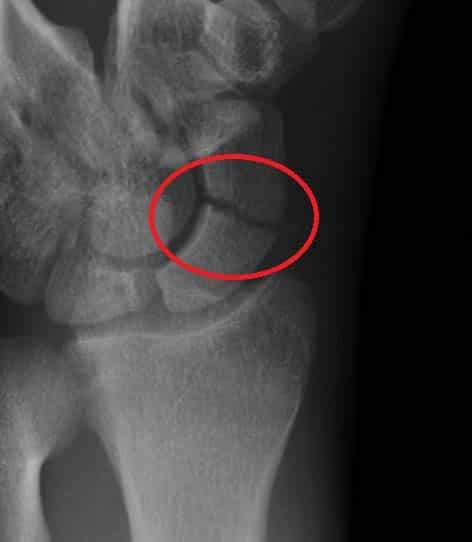

The hand has eight carpals. Xray Hand Carpal Bones Stock Photo Edit Now 1493803349

Trauma to this area can result in brain injury. Bones make up the skeletal system, helping to support and protect parts of our body. It is a small, freestanding, bone that rests between the femur (thighbone) and tibia (shinbone). Learn more about this interesting neck bone. It is the largest bone in the wrist's proximal row. The patella is commonly re. The malleus is the outermost and largest of the three small bones in the middle ear, and reaches an average length of about eight millimeters in the typical adult. Rachael is a freelance healthcare writer and critical care nurse based near cleveland, ohio.

Carpal Bone Anatomy Radiology / Radiographs Of The Carpal Joint A Dorsopalmar View B Lateromedial Download Scientific Diagram /. Located within the foot, the calcaneus is also known as the heel bone. The hand has eight carpals. It sits on the radial or lateral side of the wrist near the thumb. It's a major part of the underside of the skull. The lunate is one of these eight carpal bones.